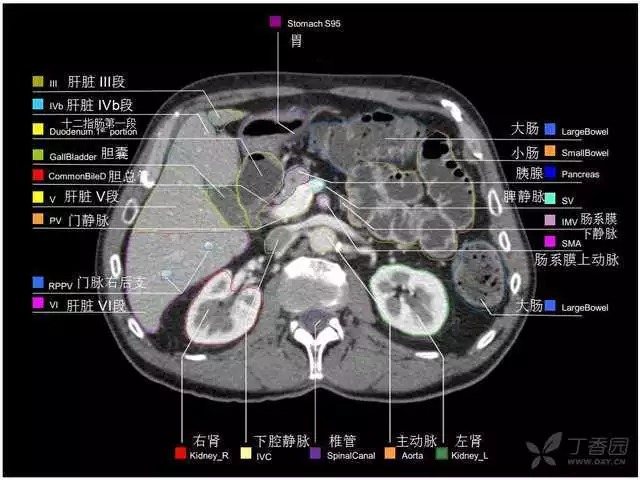

腹部肝脏高清CT断层的图谱

全腹部高清CT图谱,淋巴结彩色图谱,血管解剖图谱大汇总!